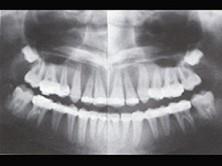

问题 患者,女,40岁,因牙齿松动脱落、失眠、食欲不振1个月来院诊治。查体:表情淡漠,牙槽骨处有压痛。骨骼X线摄片和I放射性核素检查结果如图所示,请问:该病例最可能的诊断为()

选项 A.骨质疏松 B.神经官能症 C.甲状旁腺功能亢进症 D.弥漫性脱钙 E.甲状旁腺减退症

答案 C